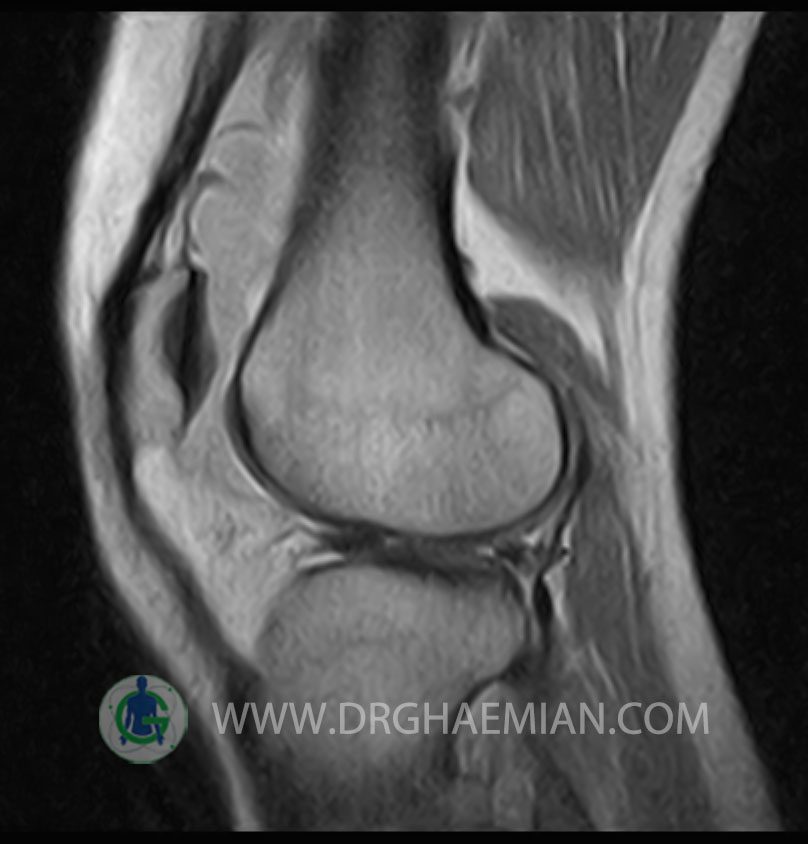

RIGHT KNEE MRI

(Without contrast)

Technique: Sagittal T1, T2 , Axial GE , coronal & sagital fatsat .

The bones comprising the knee joint are normal in configuration.

The cortical bone has normal thickness.

The hyaline cartilage covering patella, fermoral condyles and tibial plateau shows normal signal and thicknees.

PCL ,MCL & LCL are intacted.

Patellar ligamentum and quadriceps tendon are normal in shape and signal intensity .

– Knee joint effusion with soft tissue swelling around the knee

– Grade 2 signal change in P.H. of medial meniscus with partial tearing of posterior root & meniscal extrusion

– Grade 2 signal change in P.H. of lateral meniscus with meniscal extrusion

– Complete tearing of ACL ( femoral detachment ) with bone bruise in plateau of tibia

are seen